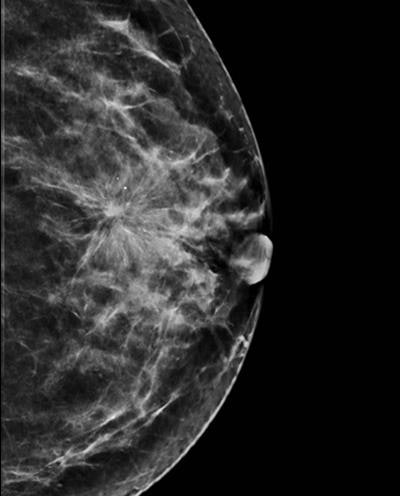

En cas d'anomalie, les radiologistes peuvent effectuer un examen complémentaire et notamment la DBT, qui, jusqu'à présent, n'est pas autorisé à des fins de dépistage systématique en raison d'une irradiation supplémentaire s'ajoutant à la dose reçue lors de la mammographie standard.

La DBT est validée pour le diagnostic en cas de résultats anormaux, comme dans la plupart des pays européens. Cependant, la Haute Autorité de Santé (HAS) devrait publier cette année une directive officielle sur l'utilisation de la DBT à des fins de dépistage, après avoir reçu une revue de la littérature sur les performances de la modalité.

Présentant un aperçu de la revue de la littérature lors des JFR 2019, Ceugnart a déclaré que la combinaison de la mammographie et de la DBT semblait produire de meilleurs taux de détection que la mammographie seule. Cependant, des études complémentaires sont nécessaires pour obtenir des résultats plus robustes, notamment en termes de taux de cancer d'interval. Il a également évoqué la possibilité d'images de synthèse générées à partir d'ensembles de données DBT afin d'éviter une exposition supplémentaire aux radiations.